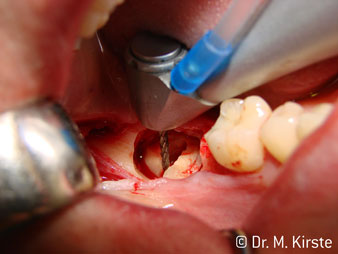

Если кратко перечислить удобства в работе: инструмент может развивать скорость до 100000 об/мин, профессионально выполненная система охлаждения и небольшая кнопка головки.

Профессиональная конструкция подшипников внутри головки обеспечивает тихую работу бора; впечатляет атравматичное разделение зуба и корня (рис. 4-9).